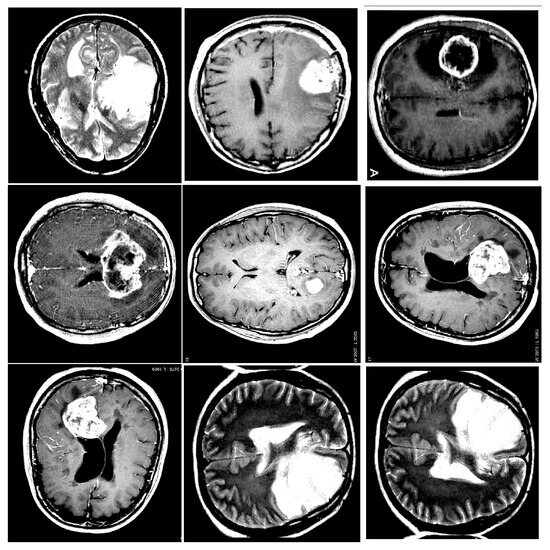

Comparative Study of MRI Modality Embeddings for Glioma Survival Prediction

by Fatima-Ezzahraa Ben-Bouazza, Saadia Azeroual, Bassma Jioudi and Zakaria Hamane

Eng. Proc. 2025, 112(1), 57; https://doi.org/10.3390/engproc2025112057 - 30 Oct 2025

Accurately predicting survival within patients diagnosed with diffuse glioma remains one of the most difficult issues in neuro-oncology. While most prior research has focused on multimodal fusion or clinical data, we introduce a modality-specific deep learning framework that employs preoperative MRI only to [...] Read more.

Accurately predicting survival within patients diagnosed with diffuse glioma remains one of the most difficult issues in neuro-oncology. While most prior research has focused on multimodal fusion or clinical data, we introduce a modality-specific deep learning framework that employs preoperative MRI only to predict mortality outcomes using patient MRI scans. Using the UCSF-PDGM dataset containing structural, diffusion, and perfusion imaging of 495 glioma patients, we trained VGG16 models on every MRI modality individually, including T1, T2, FLAIR, SWI, DWI, ASL, HARDI-derived metrics, and segmentation maps. Our findings revealed that segmentation-based and diffusion-derived features, particularly FA or tensor eigenvalues, possessed the greatest predictive strength, surpassing those obtained from standard structural MRI in binary survival classifications. This approach of modality-specific model training allows for clearer explanations of the prediction process compared to fused approaches and is more practical in scenarios where not all types of MRI are performed on patients. This approach demonstrates the strong predictive power of individual MRI sequences for mortality in glioma cases, providing a modular, adaptable, and clinically actionable deep-learning framework. Additional enhancements can incorporate volumetric models, longitudinal imaging, and non-imaging datasets, including genomic and clinical information. Full article